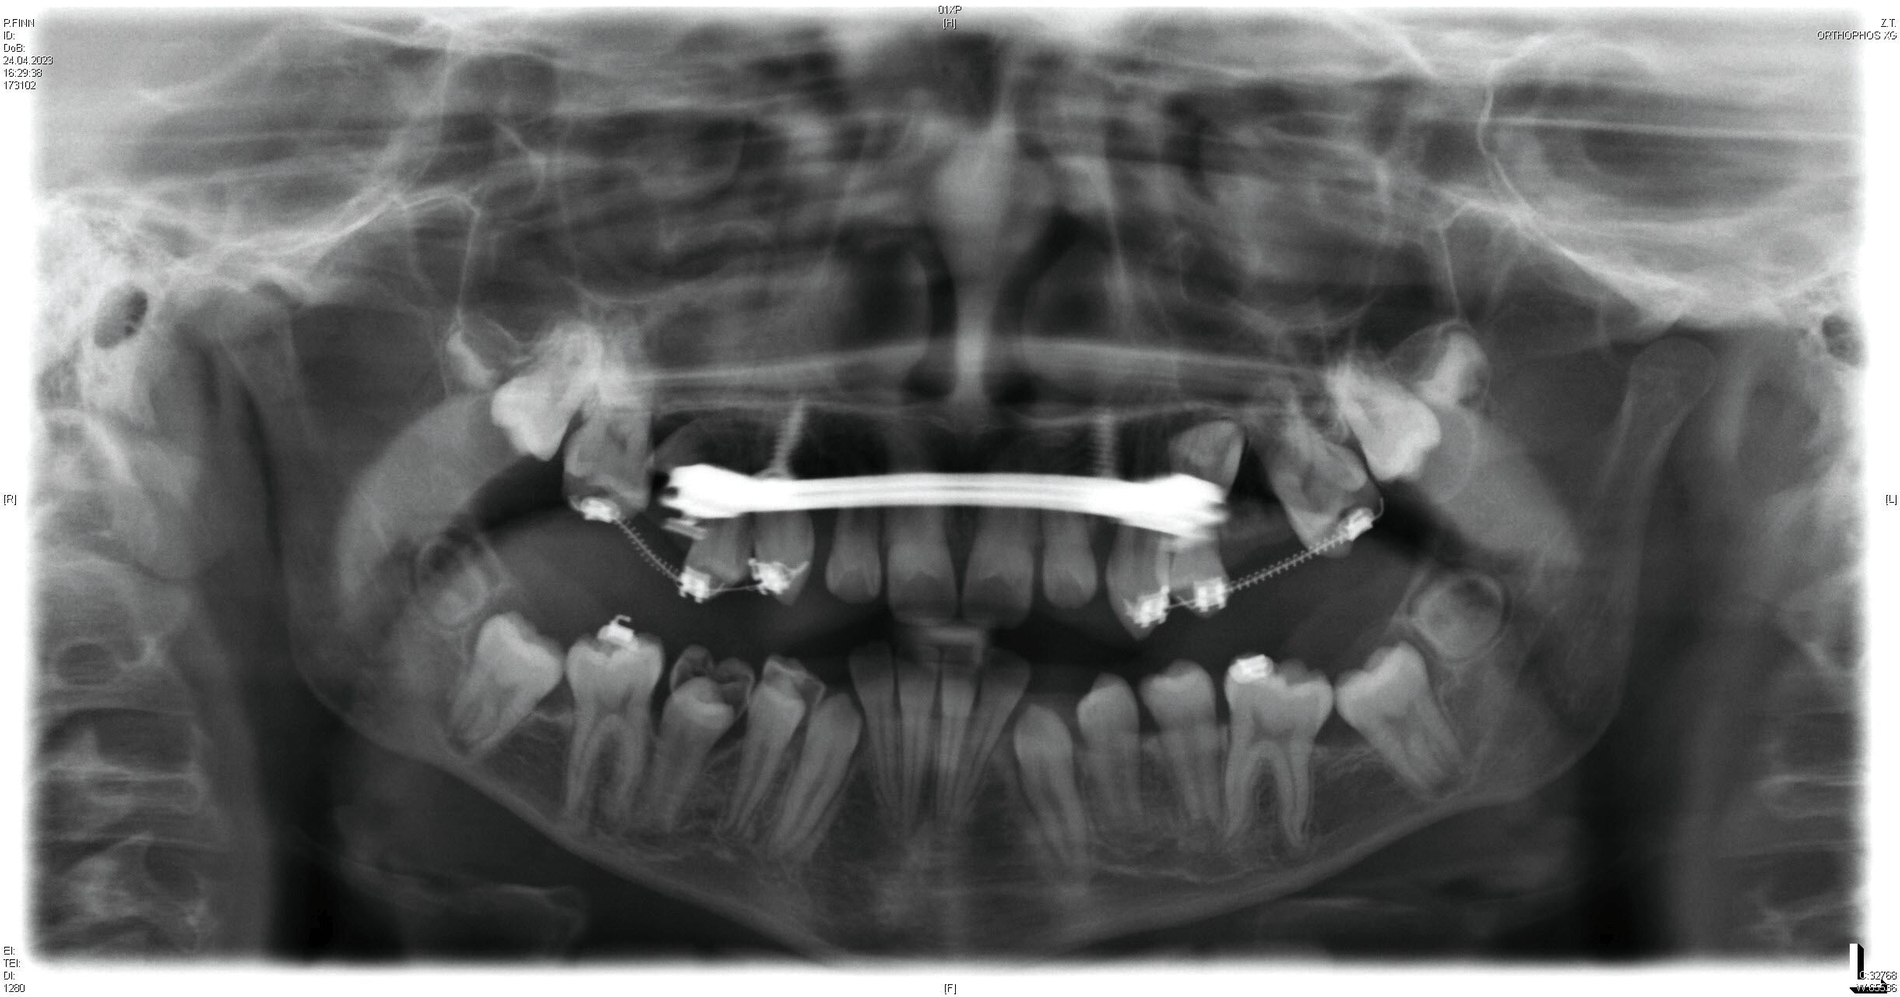

Die initiale Panoramaschichtaufnahme zeigte die Verlagerung mehrerer Zahnkeime sowie einen Platzmangel der Eckzähne und der Prämolaren im Oberkiefer (Abbildung 1b). Die Keimkrone von Zahn 13 wies dabei eine enge Lagebeziehung zum Zahnkeim 12 auf (Abbildung 1b). Die bereits eruptierten permanenten Frontzähne zeigten eine Angulations- und eine Inklinationsfehlstellung. Im distalen Bereich waren keine Durchbruchshindernisse erkennbar. Vor Beginn der kieferorthopädischen Behandlung wurde eine Primäre Zahndurchbruchsstörung (Primary Failure of Eruption – PFE) genetisch ausgeschlossen.

Das Endergebnis ist in der Panoramaschichtaufnahme in Abbildung 6 gezeigt, in der beide Mini-Implantate keine Anzeichen einer periimplantären Osteolyse aufweisen. Während des Behandlungszeitraums von insgesamt 31 Monaten wurden keine unerwünschten Nebenwirkungen beobachtet.